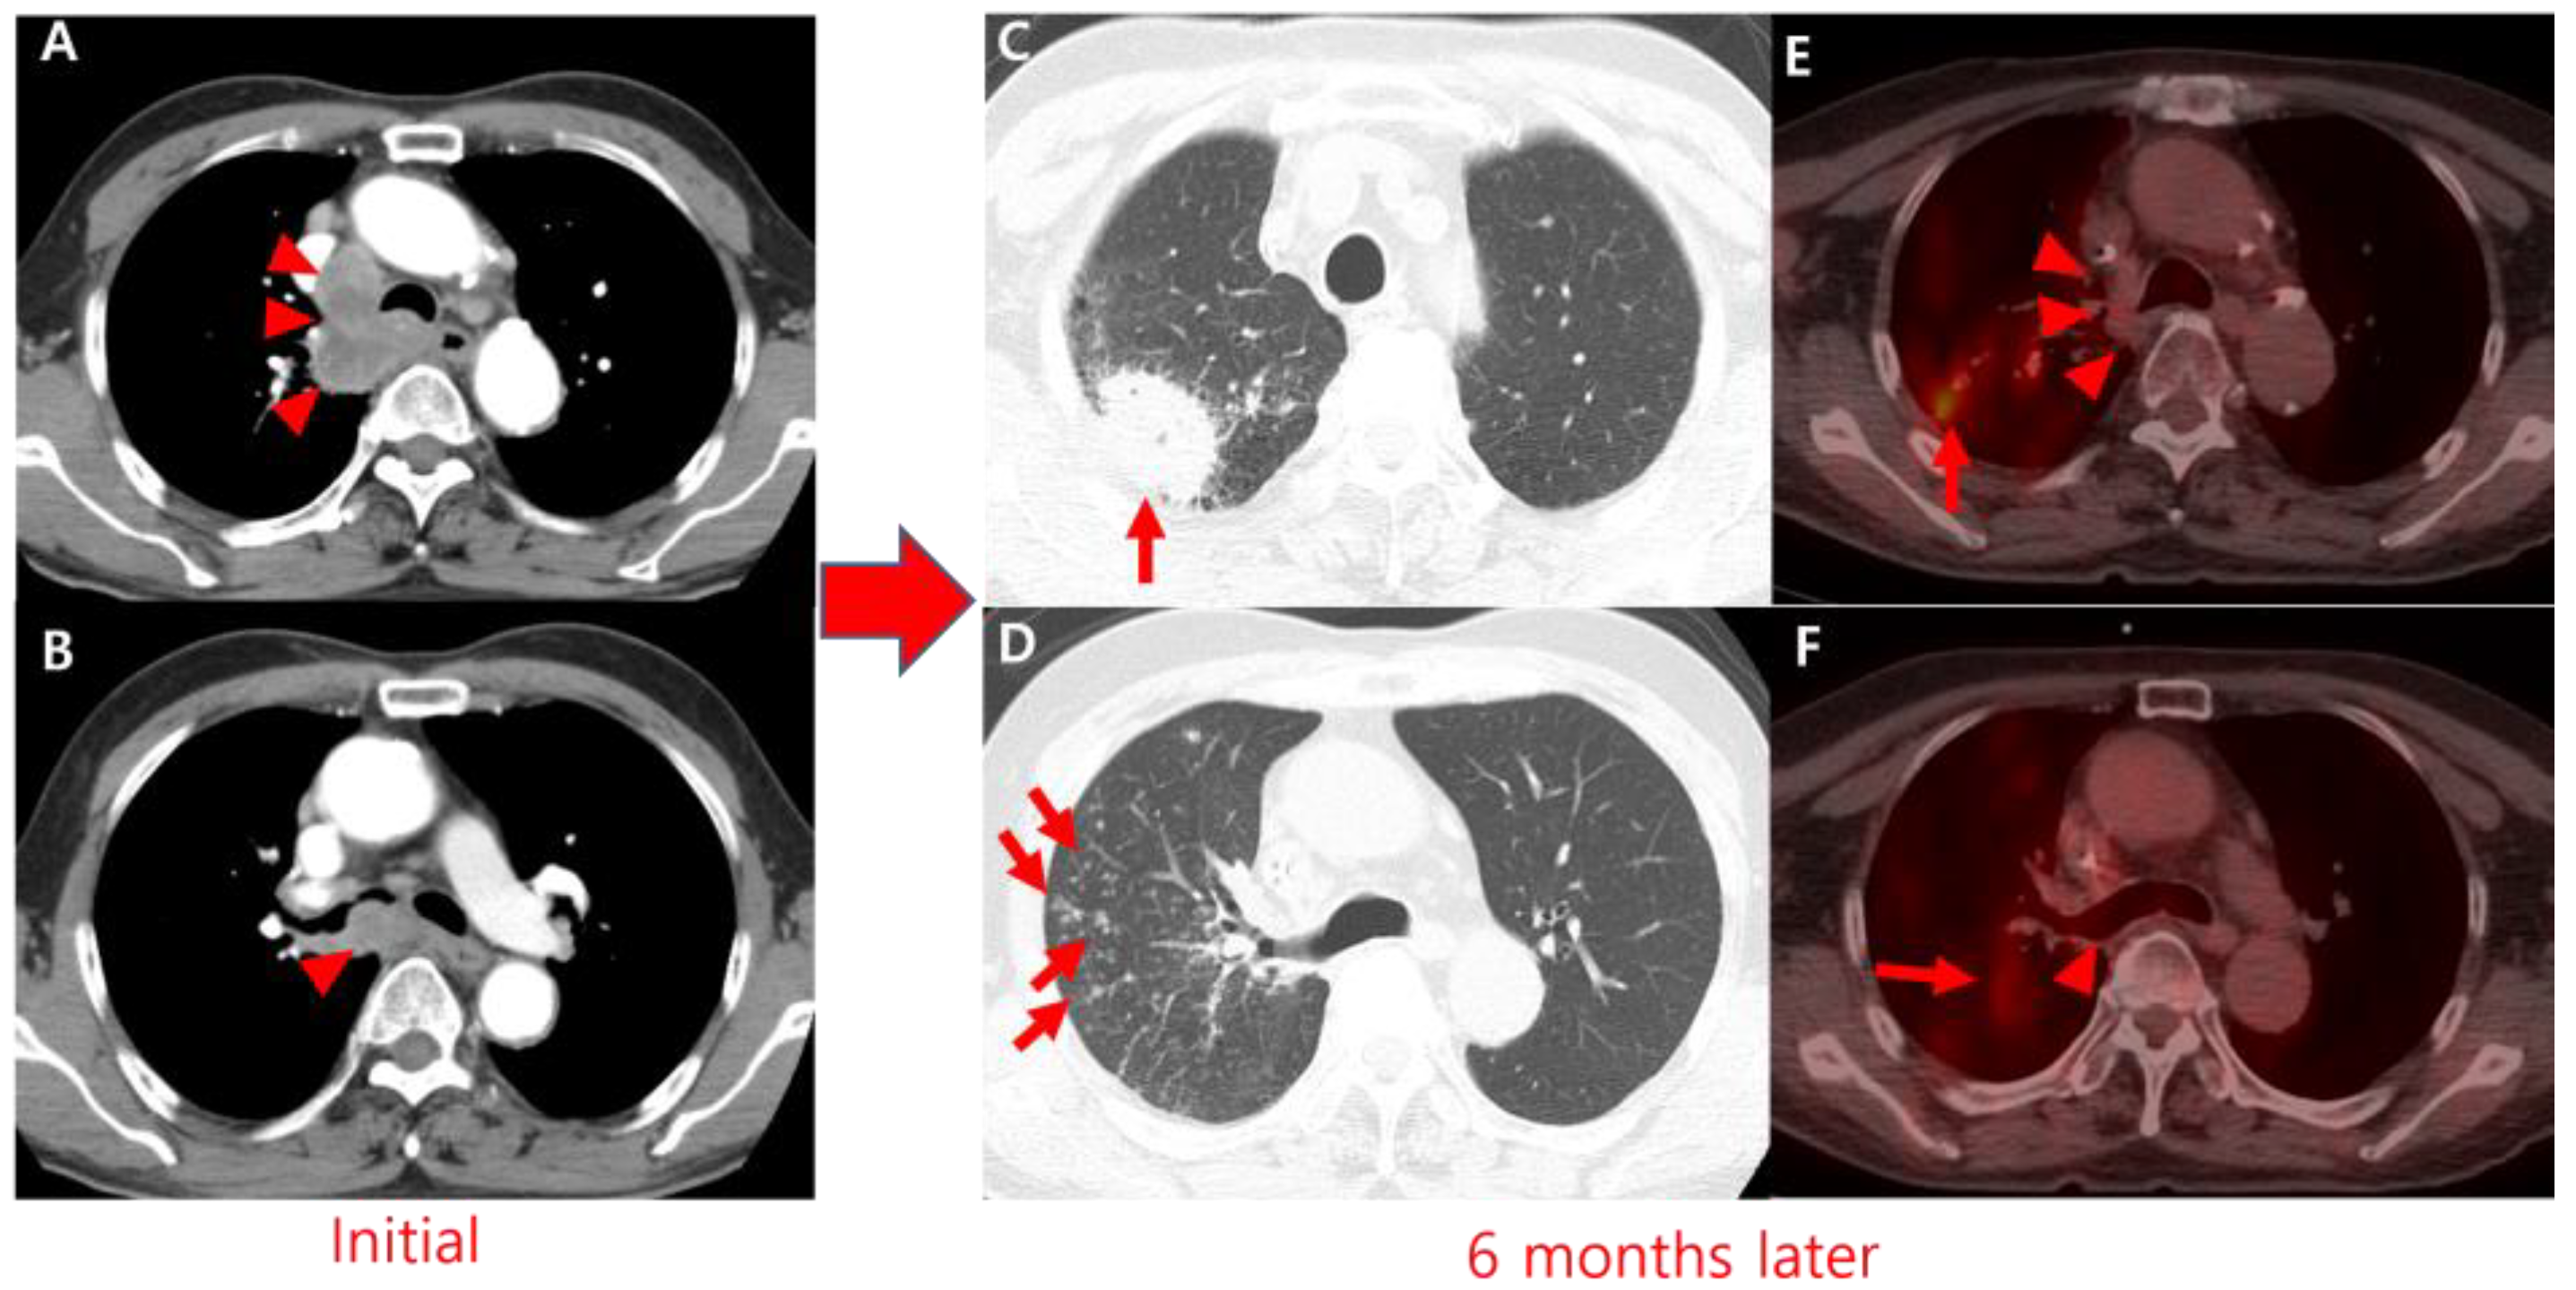

Paradoxical Reaction to Antituberculosis Therapy Mimicking Tumor Progression in Lung Cancer Patient